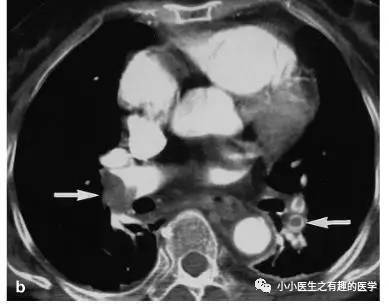

上面图片的英文原版:

病例介绍二:

作者单位:Department of Radiology, University of Washington MedicalCenter, University of Washington School of Medicine。华盛顿医科大学。

翠花上菜,学者上图。

发现嫌疑犯,立即逮捕。

增强CT对比,一目了然。

上面的病人,增强CT放大了。